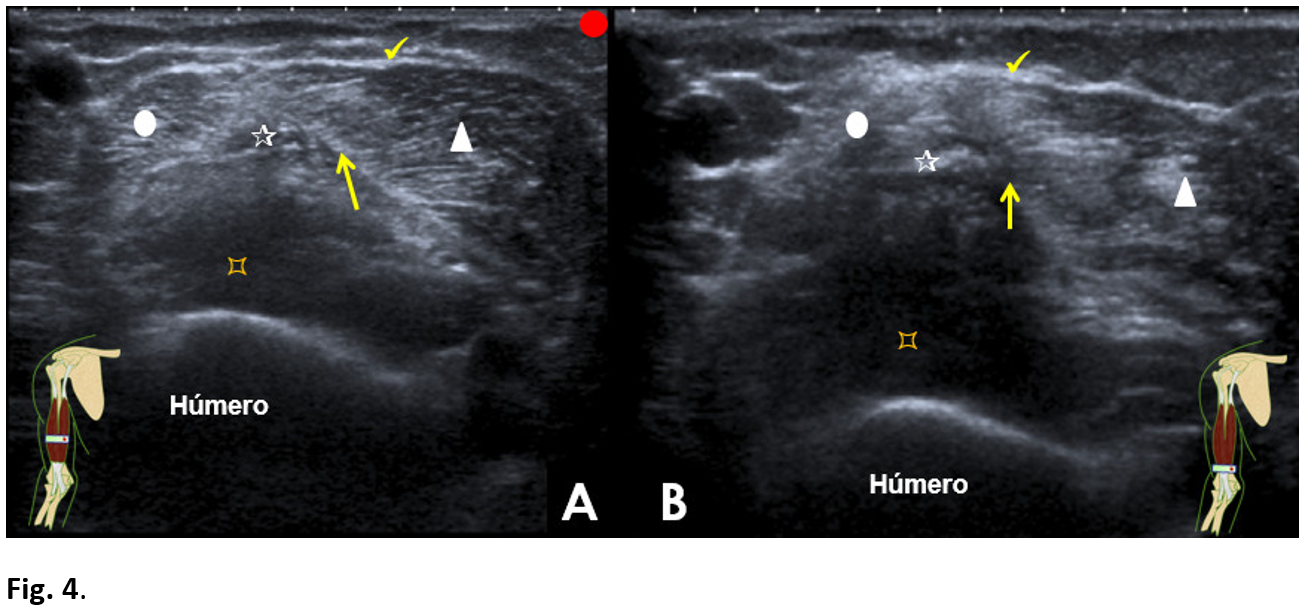

In the axial or transverse section on the distal third of the forearm (Fig. 4A and B), a significant atrophy of the long (outermost) portion was observed. In the immediate deep plane, the hyperechogenic, stellate, retractable image corresponds to the fibrous scar.

Figure 4: Over the most distal portion of the biceps brachii muscle

Axial incidence. Long head of the bíceps brachii muscle (white circle). The fibrous scar (star). Retraction of the central tendinous septum (arrow). Anterior brachial muscle (pointed square). The bicipital aponeurosis (tick).

In the most distal axial section. Fibrous scar (star). The distal myotendinous junction of both muscular portions (short (white circle) and long (white triangle)).